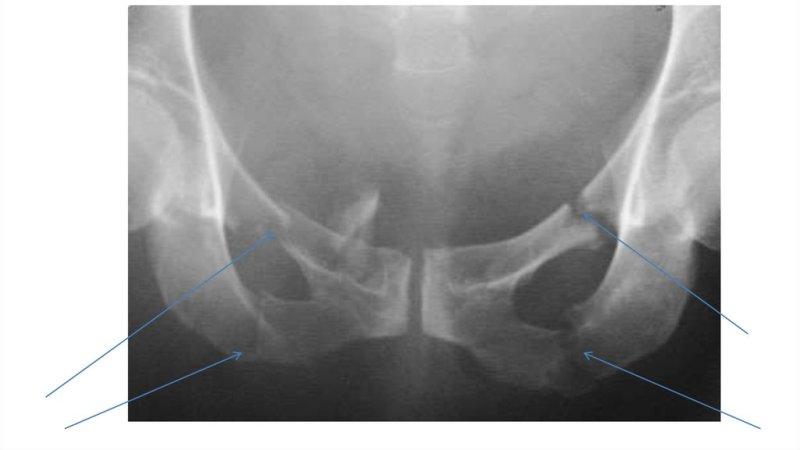

- рентгенография (обзорный снимок, фото лобковой кости);

- МРТ, КТ (при надобности).